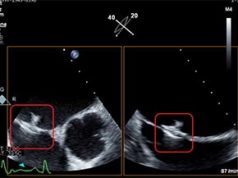

Vectorious Medical Technologies developed a miniature pressure sensor that is implanted within the heart via standard minimally invasive transvenous catheterisation. The sensor measures left atrial pressure (LAP), the earliest and most accurate indicator of fluid overload and congestion status.